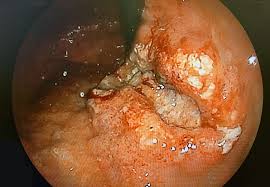

(1) 위내시경 검사

가장 중요한 진단 도구이며, 직접 위 내부를 관찰하고 의심 부위를 조직검사(생검)할 수 있다.

(2) 조직 생검

내시경 중 의심 부위 조직을 채취하여 현미경으로 암세포 유무를 확인한다.